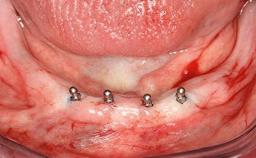

After flapless tooth removal and a healing period of 6 weeks a diameter-reduced two-piece implant is placed. The bone defect on the facial aspect is corrected with a contour augmentation using autologous bone chips covered with DBBM particles and a collagen membrane according to the Guided Bone Regeneration (GBR) approach.

Bone Augmentation Horizontal|Simultaneous

Augmentation Materials Autogenous chips|Xenogenous|Membrane

Bone Volume Deficient horizontally, allowing simultaneous augumentation